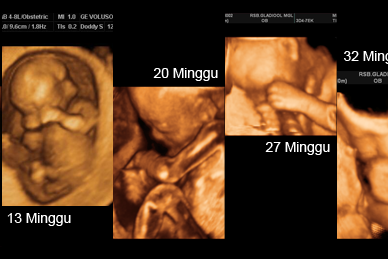

Perkembangan Janin Usia 6 Bulan - Bidanku.com Perkembangan Janin 6 Bulan (24 Minggu) - Hamil.co.id Hamil 6 Bulan, Begini Penampakan Janin dalam Kandungan Perkembangan Janin Usia Hamil 6 Bulan Dalam Kandungan | Proses perkembangan janin dari usia kehamilan 1 bulan hingga 9 bulan | theAsianparent Indonesia Hamil 6 Bulan, Begini Penampakan Janin dalam Kandungan Perkembangan Janin Kandungan: Ini 9 Tahap yang Perlu Kamu Tahu 4 Periode Perkembangan Janin di Kehamilan 6 Bulan | Ibu Feather Blog Foto: Perkembangan Janin dalam Kandungan dari Bulan ke Bulan - kumparan.com Perkembangan Janin 6 Bulan | Dr. Teagan Taylor Perkembangan Janin Usia 6 Bulan, (21-24 Minggu) - Hamil Sehat Tips Proses perkembangan janin dari usia kehamilan 1 bulan hingga 9 bulan | theAsianparent Indonesia Apa Yang Terjadi Di Usia Janin 7 Bulan? - kumparan.com Gerakan Janin 6 Bulan - Dunia-Ibu.org Bentuk Janin Usia 6 Bulan - YouTube Posisi Janin Usia 6 Bulan Dalam Kandungan | Proses perkembangan janin dari usia kehamilan 1 bulan hingga 9 bulan | theAsianparent Indonesia Berat Normal Janin Usia 6 Bulan Dalam Kandungan | Perkembangan Janin 6 Bulan, Baby Sudah Bisa Diajak Ngobrol Lho Moms Ini Perkembangan Bayi dalam Kandungan dari Minggu ke Minggu - Alodokter SEPUTAR DUNIA: TUMBUH KEMBANG JANIN DALAM RAHIM Begini Perkembangan Janin Usia 27 Minggu Perkembangan Janin - Hamil 6 Minggu | Enfa Berat Janin di Usia Kehamilan 6 Bulan | HonestDocs Bayi di Cirebon Lahir Dalam Usia Kandungan 5 Bulan - Regional Liputan6.com Foto Perkembangan Bayi Kembar di Dalam Rahim Ibu Hamil - kumparan.com Kisah Pilu Bayi Berjuang untuk Hidup, Saat Lahir di Usia Kandungan 6 Bulan Hanya Sebesar Botol Kecap - Serambi Indonesia Perkembangan Janin Usia 4 Bulan Dalam Kandungan (17-20 Minggu) - ANTVKLIK Tahapan Perkembangan Bayi 9 Bulan dalam Kandungan | Prenagen Perkembangan Janin Usia 6 Bulan (Tips Hamil 6 Bulan) 2020 Ibu Hamil Wajib Baca. Inilah 4 Jenis Posisi Bayi dalam Kandungan dan Cara Persalinan Terbaiknya USIA JANIN 6 BULAN - Jenis Kelamin Sudah Terlihat - YouTube 2 Hal Berikut Ini Harus Moms Waspadai di Usia Kehamilan 6 Bulan - Semua Halaman - Nakita Usia Kandungan Telah Mencapai 6 Bulan! Berikut Cara Menjaga Kehamilan Menjelang Melahirkan-MamyPoko Indonesia Berat Janin Ideal yang Perlu Diperhatikan untuk Melihat Pertumbuhan Bayi Proses Perkembangan Janin dari 1-9 Bulan Perkembangan Janin Kandungan: Ini 9 Tahap yang Perlu Kamu Tahu Posisi Bayi Dalam Kandungan Memutar Terbalik di Minggu Keberapa? Kapan Rambut Mulai Tumbuh Saat Dalam Kandungan? 7 Tanda Permasalahan pada Janin | Popmama.com Perkembangan janin 7 bulan - Video pertumbuhan janin trimester ketiga | theAsianparent Indonesia Manjakani Kanza Asli Aceh: Perkembangan Janin Usia Kehamilan 8 Bulan Apa yang Harus Diperhatikan dan Dilakukan di Kehamilan 6 Bulan? - Semua Halaman - Nakita Ibu Hamil Wajib Baca. Inilah 4 Jenis Posisi Bayi dalam Kandungan dan Cara Persalinan Terbaiknya 7 Tanda Permasalahan pada Janin | Popmama.com Gugurkan Kandungan Usia 6 Bulan, Sepasang Mahasiswa Ditangkap - Berita Maluku Utara Moms, Ternyata Begini Lho Posisi Bayi Selama di dalam Kandungan Hal yang Anda Perlu Ketahui tentang Gerakan Janin Dalam Kandungan - Health Liputan6.com 9 Tanda Hamil 6 Bulan ini Wajib Ibu Ketahui - Ibupedia 4G USG BABY 6MONT,usg bayi dalam kandungan umur 5-6 bulan udah kelihatan cowok atau cewek. - YouTube Tentang Ibu - Berbagi Informasi Kehamilan Dan Tips Untuk Ibu Hamil Ibu Hamil Wajib Baca. Inilah 4 Jenis Posisi Bayi dalam Kandungan dan Cara Persalinan Terbaiknya Perkembangan Janin Usia 6 Bulan (24 Minggu) dan Bentuk dalam Kandungan Perkembangan Janin Kandungan: Ini 9 Tahap yang Perlu Kamu Tahu Tanda janin meninggal dalam kandungan - 7 hal yang perlu diwaspadai! | theAsianparent Indonesia Hitung, Berapa Kali Janin Bergerak dalam Sehari - Nakita Masa Perkembangan dan Posisi Janin Usia 6 Bulan | Prenagen Cari Tahu Berat Janin 6 Bulan yang Normal di Sini - Alodokter Perkembangan Jantung Janin dari Trimester Pertama Sampai Ketiga Kumpulan Keluhan Ibu Hamil 8 Bulan | JendelaMata.com Gambar Proses Tumbuh Kembang Bayi dalam Kandungan Ibu Hamil Wajib Baca. Inilah 4 Jenis Posisi Bayi dalam Kandungan dan Cara Persalinan Terbaiknya 6 Cara Mengatasi Bayi Sungsang Tanpa Bantuan Medis | theAsianparent Indonesia Perkembangan Janin Kandungan: Ini 9 Tahap yang Perlu Kamu Tahu Foto: Perkembangan Janin dalam Kandungan dari Bulan ke Bulan - kumparan.com Perkembangan Janin 25 Minggu Kehamilan • Hello Sehat Perkembangan Janin 5 Bulan di Dalam Kandungan, Bunda Wajib Tahu! - YouTube Perkembangan Janin 6 Bulan: Wajah Terbentuk Perkembangan Janin dan Ibu Hamil Minggu ke-26 Berat Janin di Usia Kehamilan 6 Bulan | HonestDocs bentuk janin usia 6 bulan dalam kandungan 10 Cara Mudah Prediksi Jenis Kelamin Bayi (No. 9 Paling Mudah) Tanda janin meninggal dalam kandungan - 7 hal yang perlu diwaspadai! | theAsianparent Indonesia 6 Cara Menjaga Kandungan Agar Tetap Sehat dan Kuat Ketahui Perkembangan Janin 6 Bulan, Ujung Kehamilan Trimester Dua | Popmama.com Inilah Penyebab Bayi Terlilit Tali Pusar - Alodokter Tahapan Pertumbuhan & Perkembangan Bayi Usia 0- 6 Bulan Begini Perkembangan Janin dalam Kandungan di Usia 5 Bulan 2 Hal Berikut Ini Harus Moms Waspadai di Usia Kehamilan 6 Bulan - Semua Halaman - Nakita Mencerdasan Anak Sejak Dalam Kandungan | Anakku.Net Perkembangan Dan Posisi Janin Yang Perlu Diperhatikan | Arla Indonesia Rambut Bayi Mulai Tumbuh Ketika Janin Berusia 8 Minggu - Tribun Lampung Bayi dalam kandungan usia 7 bulan hilang??? Whaaaat??? | KASKUS Audrianaku | Keluarga Soffy Hartriana, drg. Cara Mengetahui Taksiran Berat Janin Sesuai Usia Kehamilan Tahapan Pertumbuhan & Perkembangan Bayi Usia 0- 6 Bulan Inilah 6 Trik yang Wajib Dilakukan jika Gerakan Janin Berhenti | Popmama.com Hamil 6 Bulan: Bayi Dapat Diajak Berinteraksi - Alodokter Perkembangan Bayi Usia 6 Bulan - Nutriclub Ini 11 Cara Menambah Berat Bayi Dalam Kandungan Perkembangan Janin dan Ibu Hamil Minggu ke-36 Navigate Berita Pengumuman CPNS Pendaftaran Pengetahuan Pengertian UUD Sekolah Mitra Sekolah SMP Guru Download File Guru Pelajaran Teknologi Biologi PPKN Close the sidebar tets Perkembangan Janin Usia 5 Bulan Dalam Kandungan … bayi: Gambar Bayi Dalam Kandungan 6 Bulan Ciri-ciri Kehamilan 6 Bulan yang Normal, Cek Sekarang Ya Moms - Nakita Foto: Perkembangan Janin dalam Kandungan dari Bulan ke Bulan - kumparan.com Ibu Hamil, Ini 12 Tandanya Bayi di Dalam Kandunganmu Sehat | BukaReview Bicara dengan janin - Cara berkomunikasi dengan bayi dalam kandungan | theAsianparent Indonesia 9 Ciri-Ciri Bayi Sehat [6 bulan pertama] Perkembangan Janin Bayi dalam Kandungan usia 1-40 minggu | dr. Adi SpOG Arti Janin Aktif Bergerak Sebelah Kanan - Alodokter